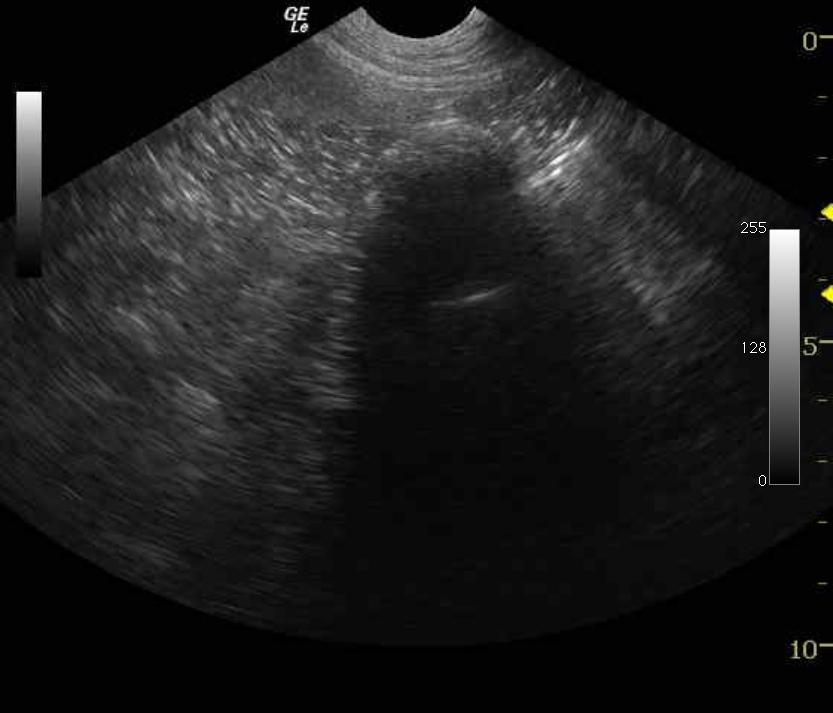

The gastrointestinal tract revealed a significant dilation of the stomach and distal small intestine with fluid material. Small intestinal obstructive material was noted measuring approximately 3.5 cm with areas of adhesion in the region caudal to the spleen. The presence of empty small intestine with dilated small intestine in the same view comprises an obstructive pattern.

Small intestinal obstructive pattern, probable foreign body, stricture, or focally compromised intestine